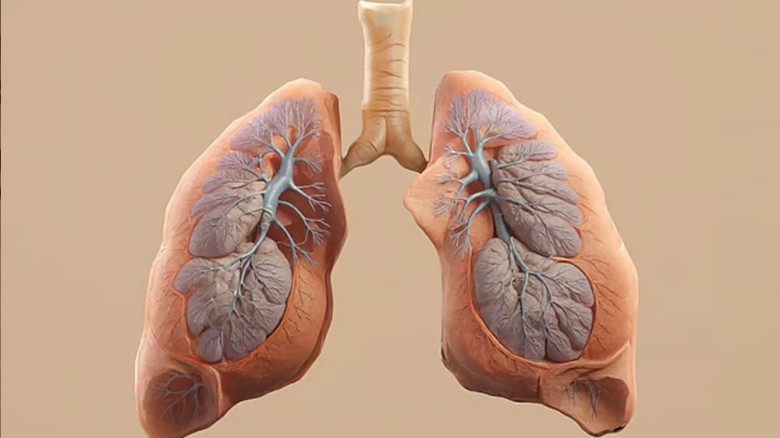

স্বাস্থ্য ডেস্ক: প্রচলিত সিগারেটের তুলনায় ই-সিগারেট বা 'ভেপ' (Vape) নিরাপদ—এমন ধারণা প্রচলিত থাকলেও সাম্প্রতিক গবেষণা বলছে ভিন্ন কথা। ই-সিগারেট সেবন থেকেও হতে পারে ফুসফুস এবং মুখের ক্যানসার। গত মার্চ মাসে আন্তর্জাতিক বিজ্ঞান সাময়িকী ‘কারসিনোজেনেসিস’-এ প্রকাশিত এক গবেষণা প্রতিবেদনে এই সতর্কবার্তা দেওয়া হয়েছে।

গবেষণায় দেখা গেছে, ই-সিগারেটের ধোঁয়ায় থাকা রাসায়নিক উপাদানগুলো ফুসফুসের কোষের ডিএনএ পরিবর্তন করতে সক্ষম, যা দীর্ঘমেয়াদে ক্যানসারের জন্ম দেয়। এছাড়া মুখের টিস্যুতে সরাসরি তাপ ও রাসায়নিকের প্রভাবে মুখের ক্যানসারের ঝুঁকিও বহুগুণ বেড়ে যায়। গবেষকেরা সতর্ক করে জানিয়েছেন, রোগ ছড়িয়ে পড়ার আগেই এ বিষয়ে ব্যাপক জনসচেতনতা গড়ে তোলা জরুরি। তথাকথিত ‘নিরাপদ বিকল্প’ হিসেবে ভেপিং বেছে নেওয়া আদতে শরীরের জন্য মারাত্মক ঝুঁকির কারণ হয়ে দাঁড়াচ্ছে।